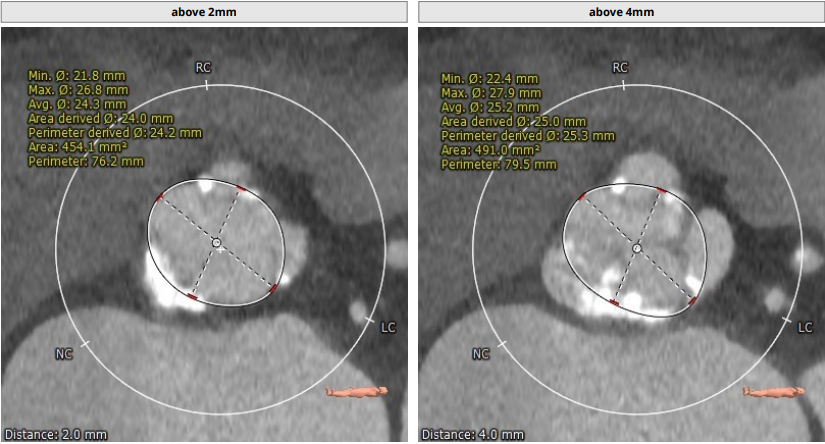

Annulus:24.4mm,LVOT:22.6mm,Asc.Ao:43.4mm,STJ:30.7mm。

瓣环结构及钙化情况:患者为TYPE 1型二叶瓣,瓣环及左室流出道呈上宽下窄型结构,钙化积分为529,主要集中于无冠窦,从基底部开始延申至左右融合处及无冠窦游离缘,整体窦部空间合适。

经聂如琼教授团队分析研判,考虑患者合并疾病复杂、虚弱等情况,拟行TAVR手术。预选20mm球囊预扩,观察球囊腰征及反流情况,以及左、右冠灌注情况。优选VenusA-Plus 26号瓣膜进行植入,观察释放完瓣膜后超声、造影评估效果。